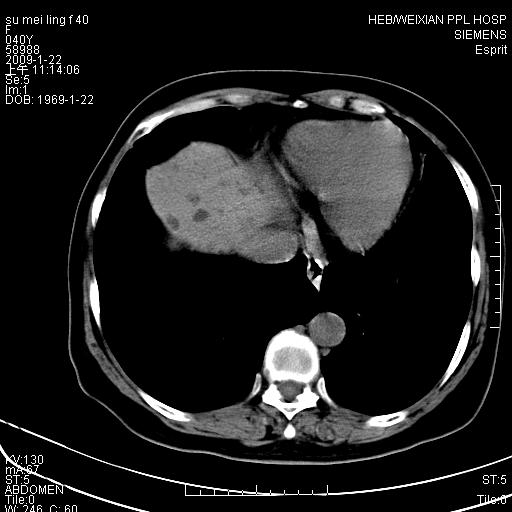

主因食欲不振检查。b超检查肝内片状低密度影。

图象的序列乱,病史也简单,单看这几幅图片考虑——肝囊肿?转移瘤?建议强化

以肝多发性囊肿可能大

我个人认为转移瘤可能性大!建议增强!

考虑多发肝小囊肿,建议增强,不排除囊性转移可能。

多发肝囊肿或caroli

肝内多发囊性低密度灶,以肝囊肿可能性大;建议必要时行进一步检查。

囊性病变沿胆管走向,首先考虑肝内胆管囊肿(caroli)、多发肝囊肿不除外